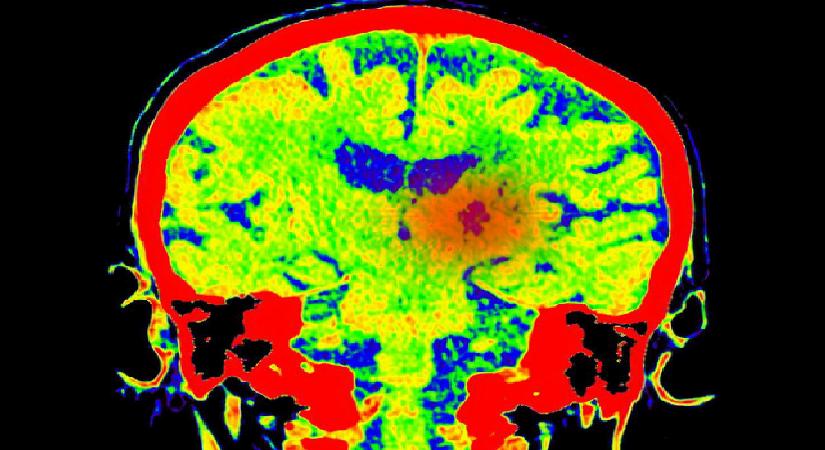

Ameliyat sonrası yapılan biyopsi, durumun varsayım edilenden daha karmaşık olduğunu ortaya koydu. Moroney’ye, çoklukla 5 yaş altı çocuklarda görülen ve yetişkinlerde rastlanması son derece az olan 4. Evre Atipik Teratoid/Rhabdoid Tümör (AT/RT) teşhisi konuldu.

Kendi yaş kümesinde bu hastalığa dair çok az hadise kaydı bulunduğu için tedavi süreci de bir o kadar belirsizleşti.

Moroney, “Danışmanım ve onkoloğum meslekleri boyunca benim yaş grubumda bu tümörle hiç karşılaşmadıklarını söylediler. Hakkında kâfi araştırma olmayan bir şeyi kabul etmek zorunda kalmak çok zor” dedi.